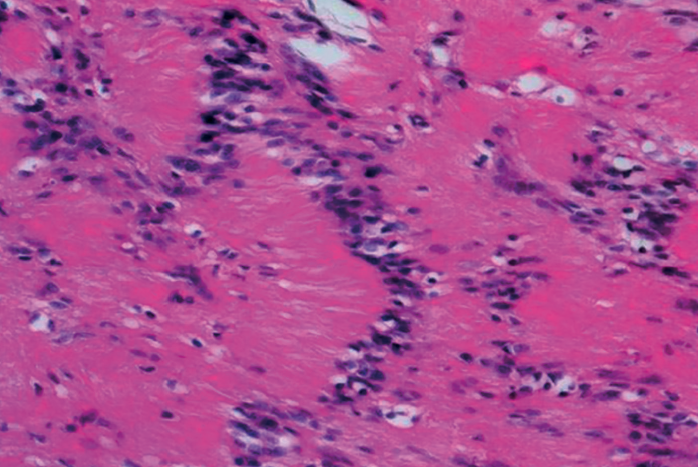

Al ampliar la imagen histológica, dentro de las zonas Antoni A, se pudieron observar células cuyos núcleos se disponen en empalizada formando los denominados cuerpos de Verocay, como nos muestra la Figura 9, siendo estos típicos pero no exclusivos de los schwannomas. En el estudio inmunohistoquímico que se le realizó obtuvimos los siguientes resultados: vimentina+, S-100+, CK (AE1/AE3−), CD45−, EMA− y Ki67 < 5%.

Los análisis histológicos y patológicos demostrarán que los schwannomas son masas fusiformes de tamaño variable y que tienen verdaderas cápsulas compuestas de epineuro (Figura 7)(8,19). La evaluación microscópica muestra que los schwannomas constan de 2 tejidos distintivos, la región de Antoni A, que es densamente celular y ordenada en haces cortos o fascículos entrelazados (cuerpos de Verocay), y la región de Antoni B, que tiene menos células y áreas desorganizadas con un mayor componente mixoide dispuestas en un estroma suelto como mostramos en las Figuras 8 y 9(9,14,19,21,28). Hao et al.(19) nos informan en su estudio, además, que cuando en la histología nos encontramos zonas de proliferación de células fusiformes concéntricas alrededor de los vasos sanguíneos con haces irregulares junto con áreas de necrosis, anaplasia y mitosis excesiva, debemos pensar en malignidad (neurofibrosarcoma), aspectos que no fueron encontrados en nuestra masa. Con respecto a la inmunohistoquímica, los schwannomas suelen mostrar una expresión fuerte y difusa de la proteína S100(29,30,31). Folpe y Gown han declarado que la inmunotinción de la proteína S100 y vimentina identifica sistemáticamente los schwannomas y que sirve como una importante herramienta de diagnóstico debido a la fuerza de su expresión(9). En el caso de nuestra paciente ambas fueron positivas y se observó abundante colágeno de tipo IV pericelular(32). Además, presentó un Ki-67 < 5%, por lo que el marcador de proliferación celular era de benignidad. Por tanto, la clínica, junto con los estudios de imagen y el estudio anatomopatológico, permitieron objetivamente diagnosticar a nuestra paciente de schwannoma benigno dependiente del NTP.

Figura 9. Microfotografía realizada con tinción de hematoxilina y eosina, donde, al ampliar una zona Antoni A, observamos un área de alta celularidad y células fusiformes con núcleos alineados formando una empalizada nuclear (cuerpos de Verocay).